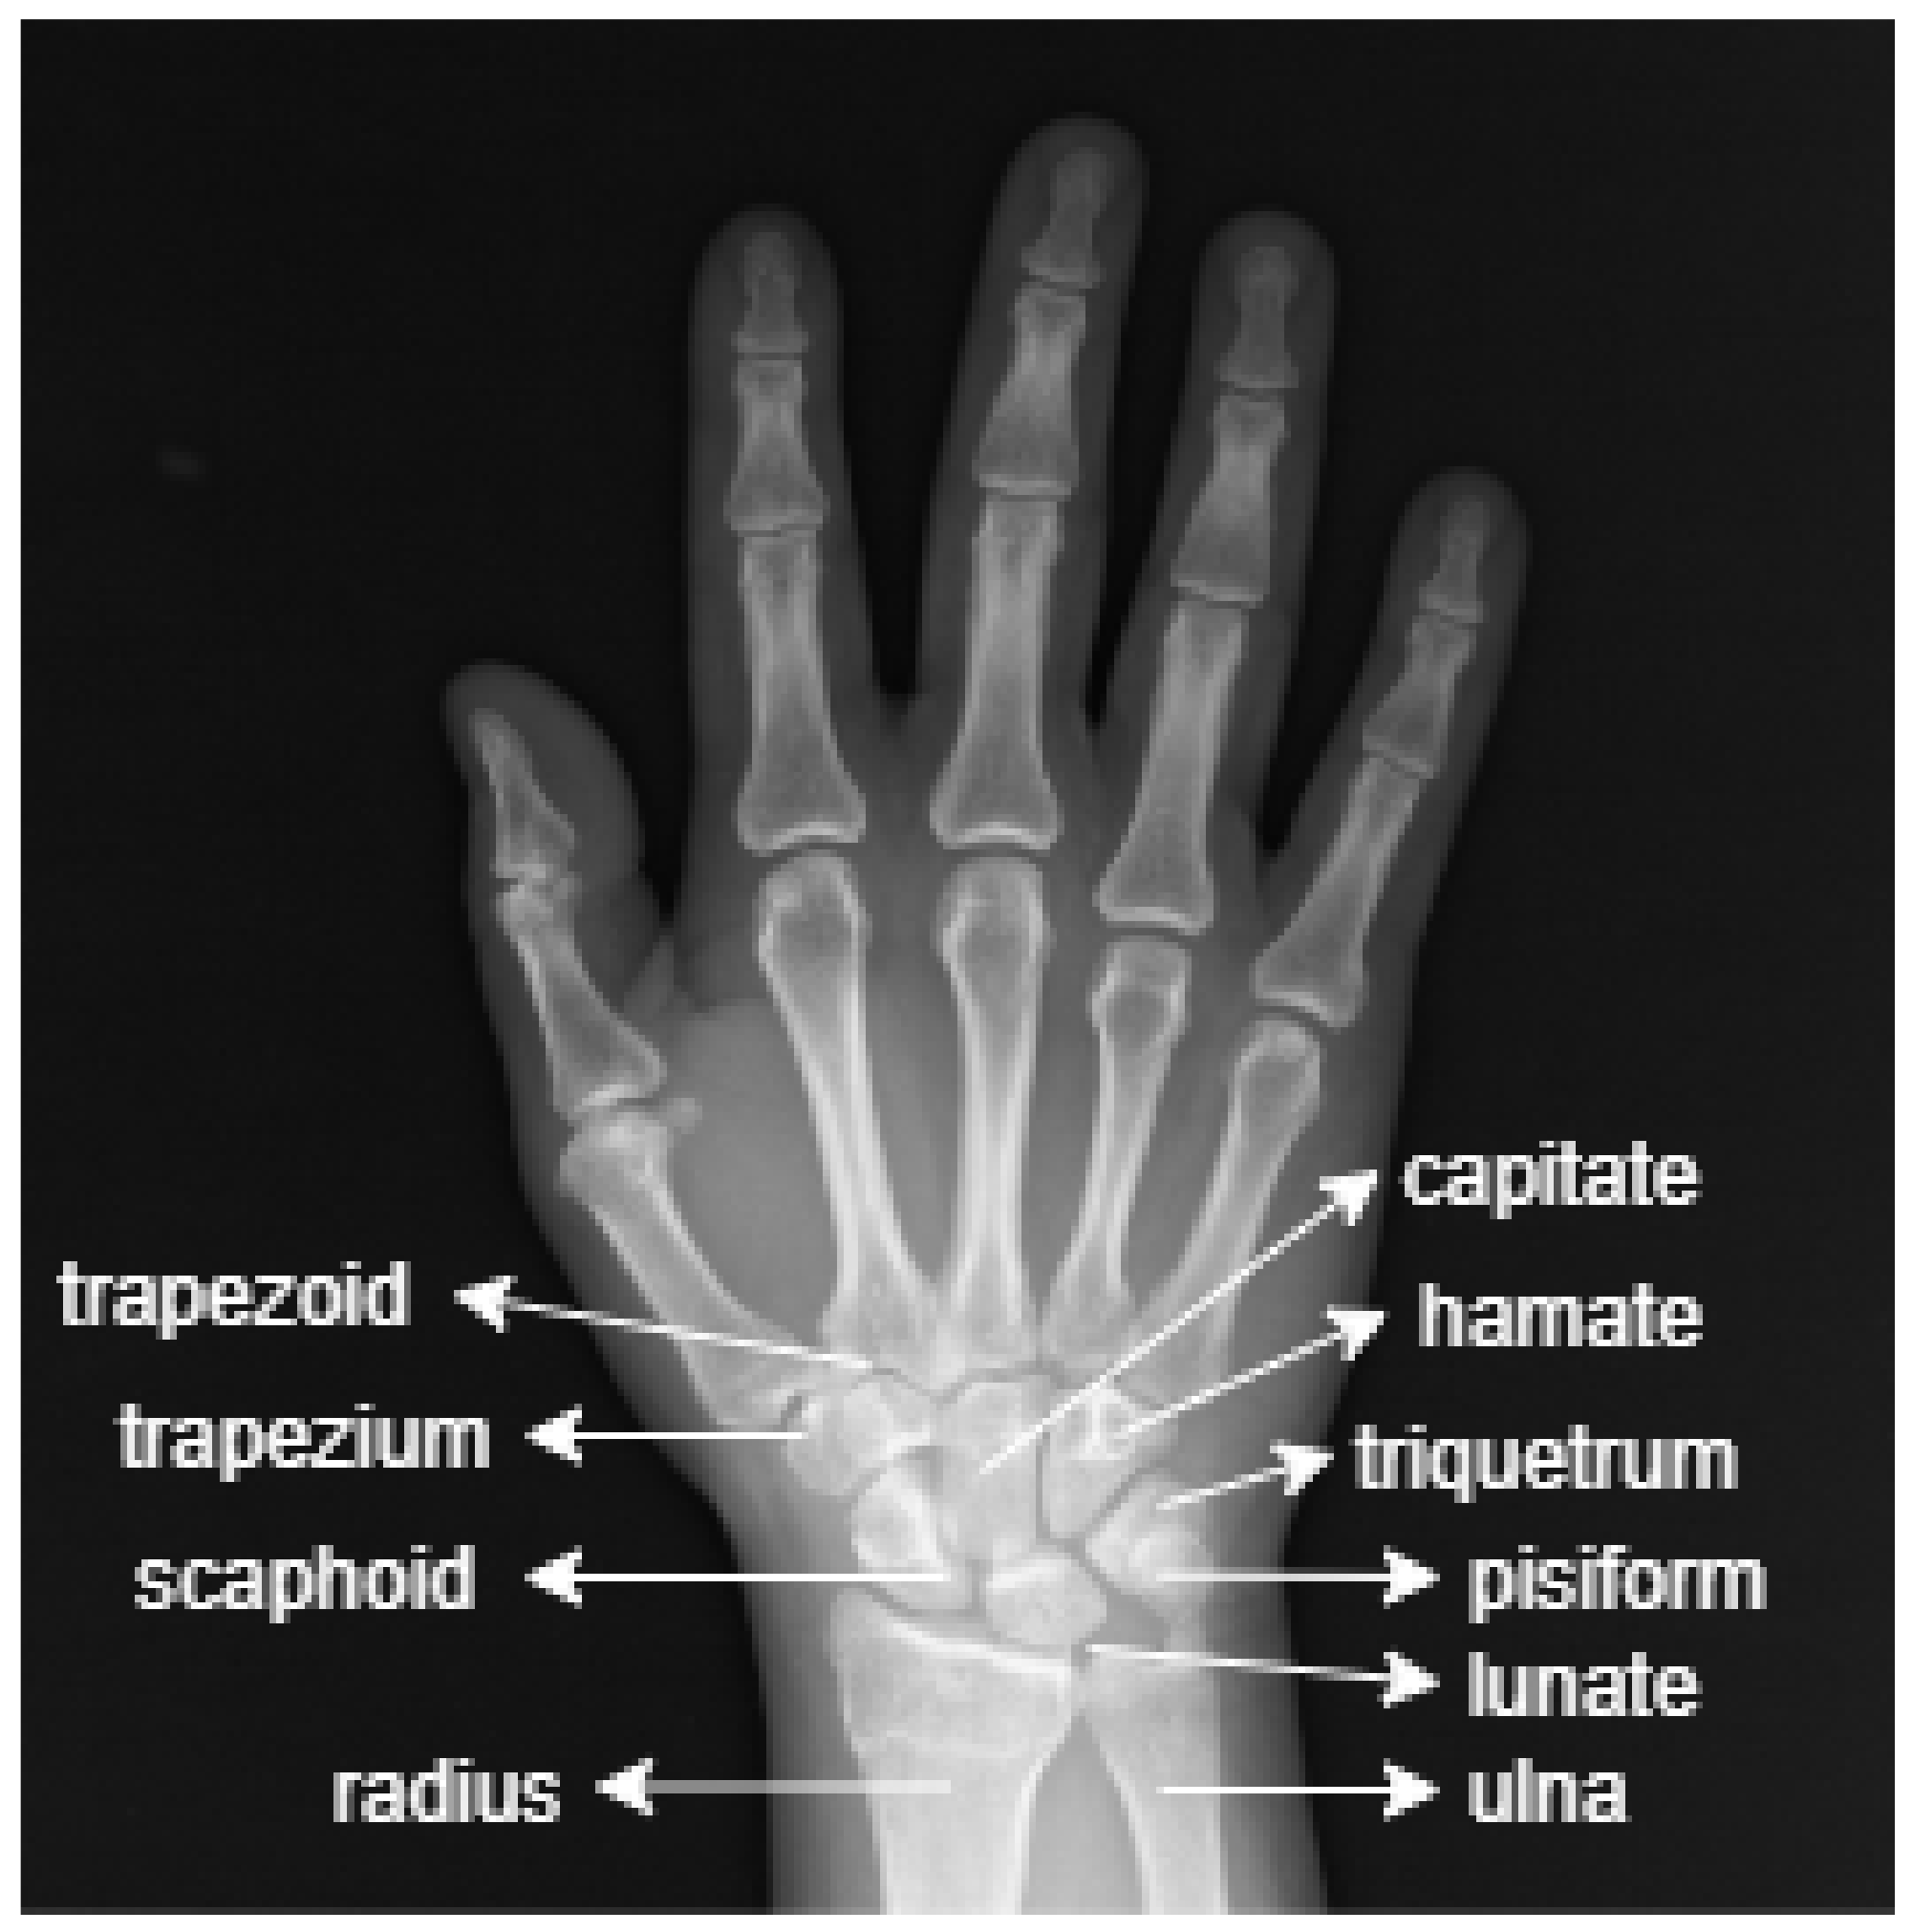

Diagnostika:

- UZI va rentgen tekshiruvi